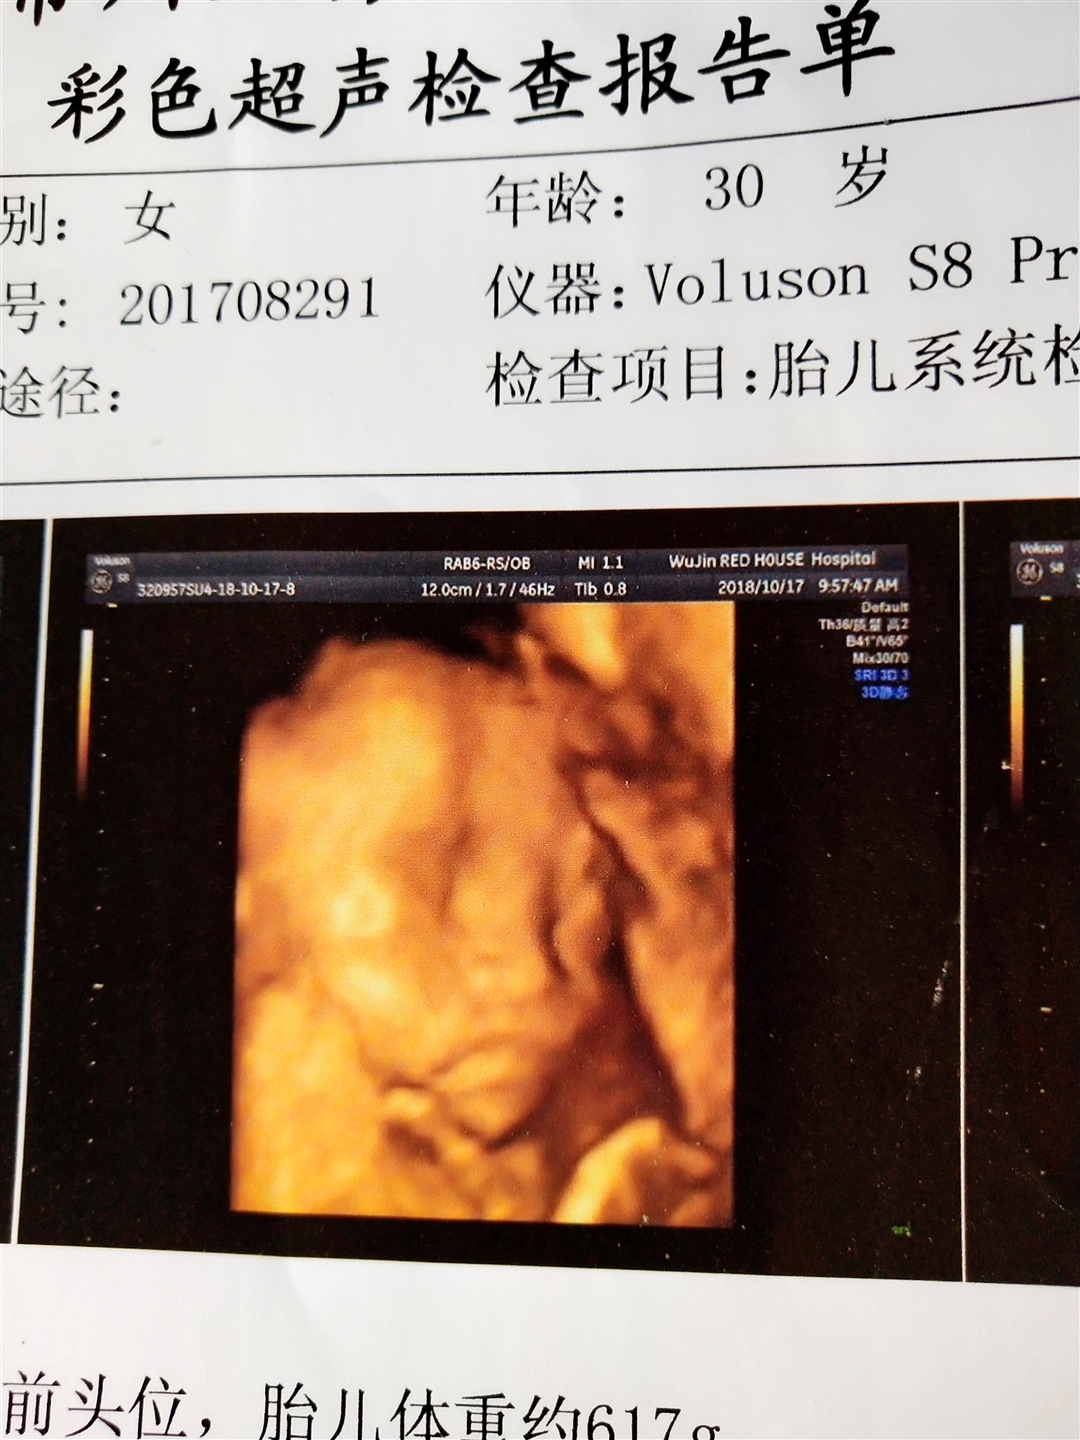

孕36周+1天

接健康女宝宝